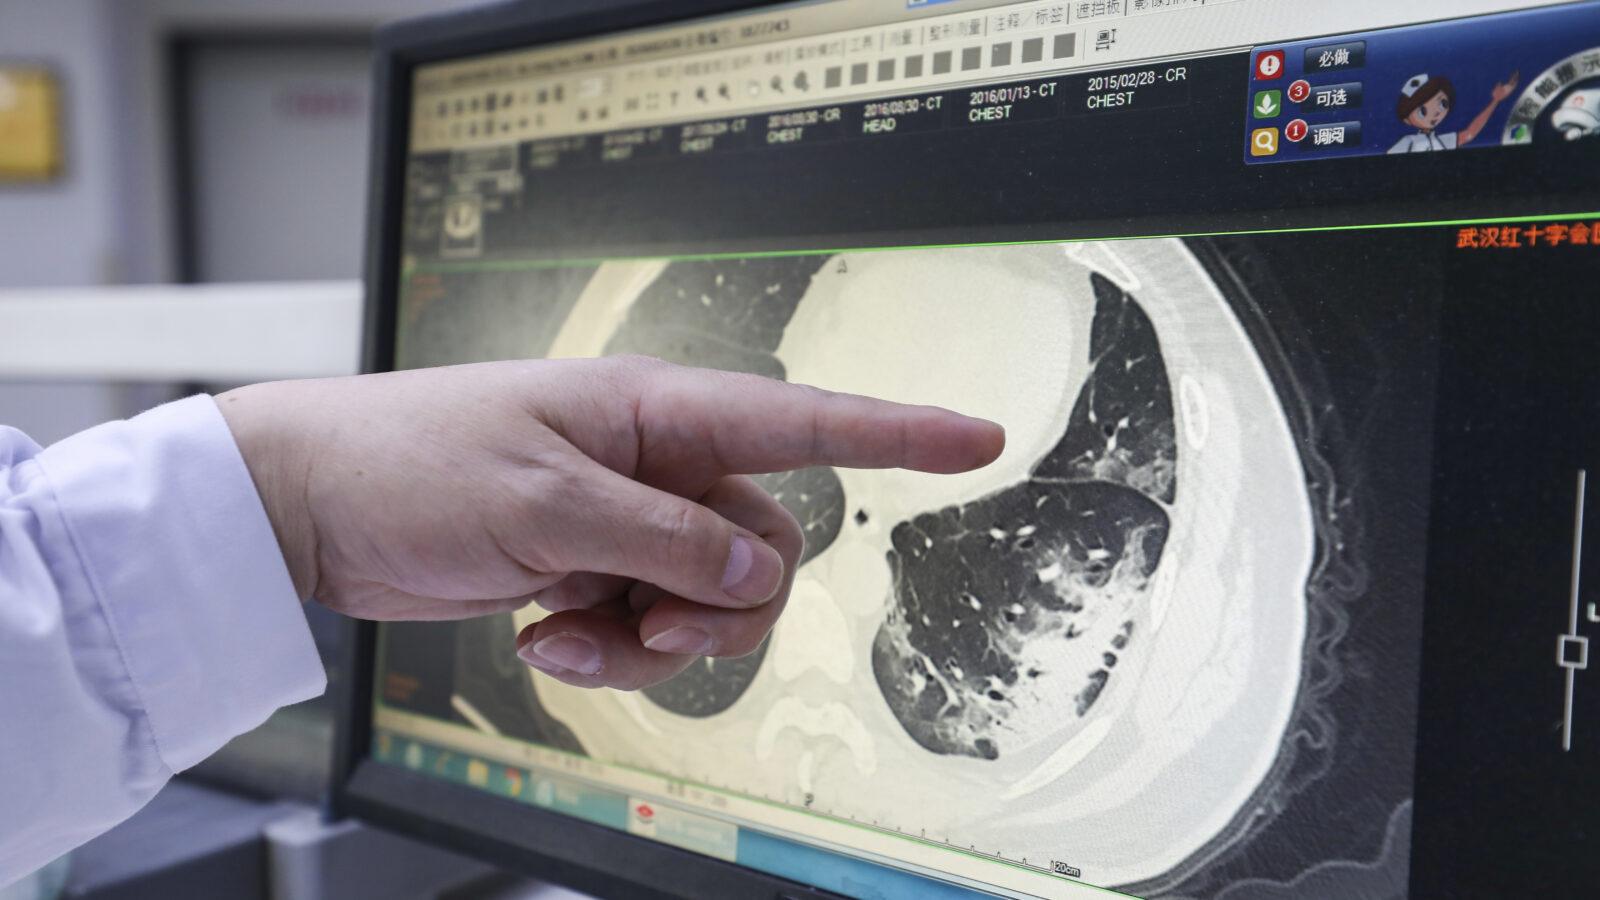

wallpaperaccess.comWhat A CT Scan Shows Of The Head & Brain

wallpaperaccess.comWhat A CT Scan Shows Of The Head & Brain

sjra.comInterior imaging uc scanner. Ct scan wallpapers. Ct scan wallpapers

sjra.comInterior imaging uc scanner. Ct scan wallpapers. Ct scan wallpapers